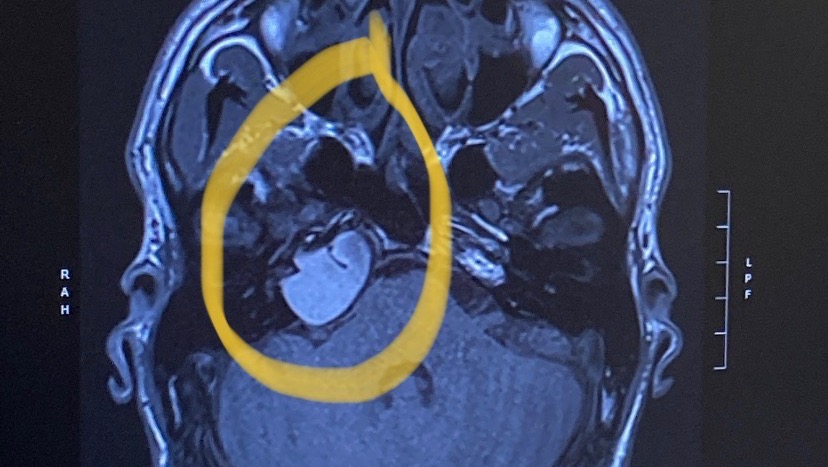

Hello everyone. My family has been struggling with some news. My husband Aaron has recently found out he has a cyst in his head that needs to be removed. Over the past couple of years, the hearing on his right side has faded out completely. Two failed hearing tests led to an MRI as well as a CT scan to discover the growth. The doctors determined that further growth of the mass could lead to more damage to nearby nerves that control facial muscles, as well as causing other serious complications. The surgeon will be able to drain the majority of the fluid inside the cyst. He will then have to take an abdominal fat graft and place it at the drain site. He is hopeful that scar tissue will prevent any further leaking or growth. The procedure will be approximately four hours long. Aaron will need to stay in the hospital for at least two days for post-surgery monitoring. The recovery time at home will be roughly four to six weeks if everything goes as planned. During this time at home Aaron will not be able to do much physical activity, being restricted to lifting no more than fifteen pounds. Because of this, he will not be able to return to work. He gets up every single morning and works harder than anyone I know. Not being able to do what he does best will bring him down. Our family has always been able to count on him to take care of us every single day. Now we need to be there for him. I would like to be able to raise enough money to help get us to Denver for the surgery as well as any follow-up appointments later down the road to recovery. The money raised will also go towards any costs not covered by insurance. Finally use some money towards bills to give my husband some peace of mind knowing he doesn't have to rush his recovery to get back to work before he's ready. We are truly humbled to be in this position. We are genuinely appreciative of any donations you can make. And if you can't make a donation that is ok. You can still help out by giving this a share. Thank you, everyone, for your love, prayers and support.